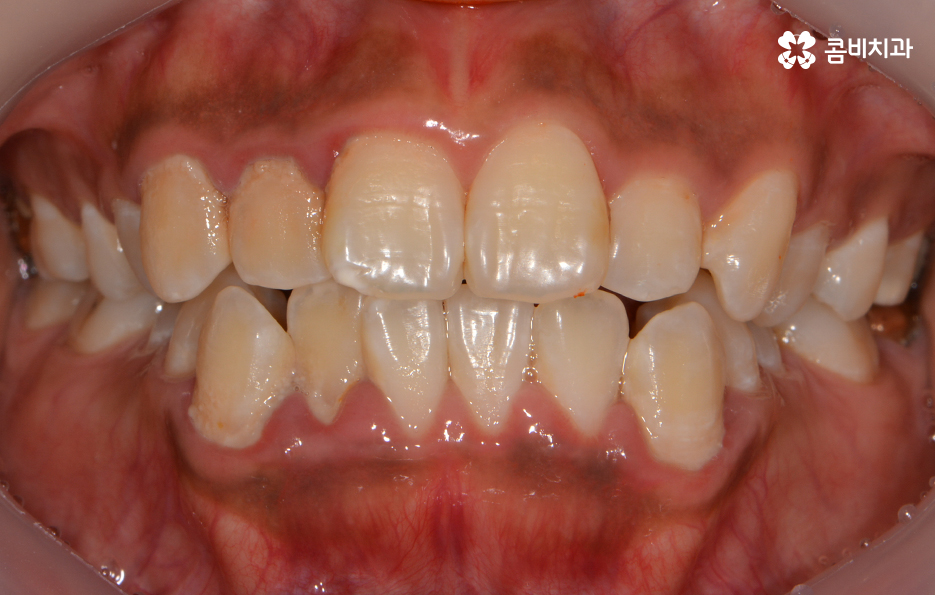

전체적인 치열의 개선을 원했고 돌출입, 아래턱 주름에 대한 고민이 있던 사례

옆모습으로 볼때 돌출된 치아로 인한 돌출입 상태